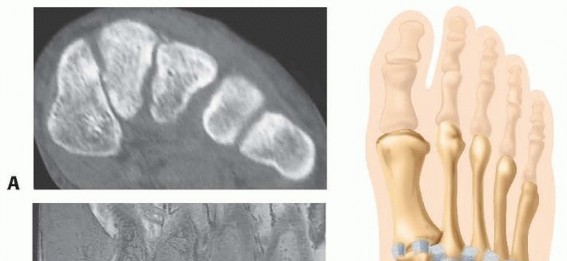

Question 15

Which of the following statements regarding hallux valgus is incorrect? an incongruent joint. during surgery.

Explanation:

A post-operative cock-up toe deformity is due to damage to the extensor hallucis longus. A post-operative cock-up toe deformity is as a result of inadvertent damage to flexor hallucis longus. The intermetatarsal angle, between the long axes of the first and second metatarsals, is normally less than 10, and is increased in hallux valgus and used to determine the severity of the deformity. The distal metatarsal articular angle (DMAA) is between the long axis of the first metatarsal and a line through the base of the distal articular cap. It is usually less than 15. In a hallux valgus deformity with a normal DMAA, the joint is incongruent, whereas in a deformity with an increase in DMAA, the joint is congruent. The dorsomedial cutaneous branch of the superficial peroneal nerve is at risk during surgery, and damage to it can result in a painful neuroma; it is best to undertake a true medial incision, rather than a dorsomedial incision.